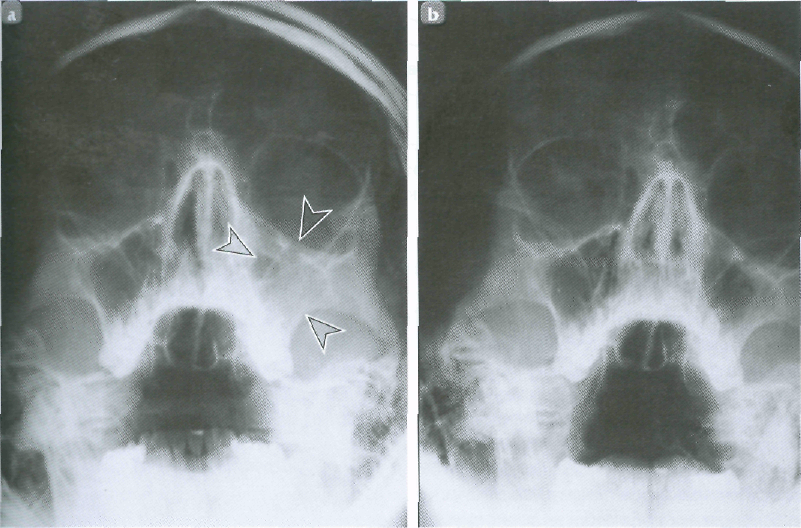

КТ-снимки хронического этмоидита: подробная визуализация